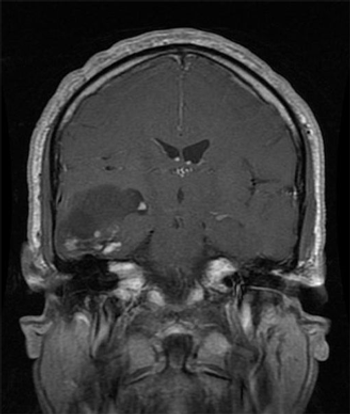

Adding rindopepimut to bevacizumab therapy was associated with improved long-term survival in patients with recurrent EGFRvIII-positive glioblastoma.